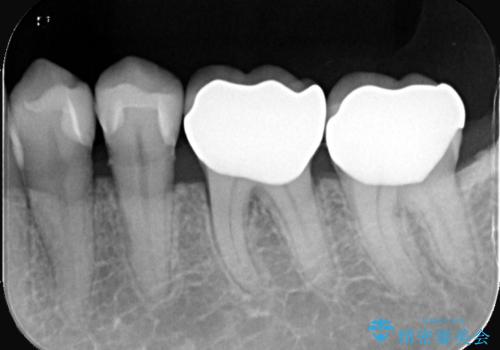

- 左下4番・5番をセラミックインレー、左下6番・7番をセラミッククラウンにより修復する集中治療を計画しました。初回に古い修復物や虫歯を除去し、精密な形成と型取りを行います。2回目に作製したセラミックインレーおよびクラウンの適合・色調を確認し、仮着を行って噛み合わせの微調整を実施します。最終3回目で調整後のセラミック修復物を完全に接着装着して治療を完了します。

今回は左下奥歯の審美性と機能性を同時に回復するため、集中治療を実施しました。左下4・5番の比較的小さな虫歯は歯質保存の観点からセラミックインレーを、左下6・7番は強度確保と噛み合わせへの負担を考慮しセラミッククラウンを選択しました。セラミックは審美性だけでなく、生体親和性も高いため、歯ぐきへの負担も少なく安全に長期使用が可能です。来院回数を3回に集約することで、患者様の負担を軽減しつつ高品質な修復を実現しました。治療後は噛み合わせの改善はもちろん、口元全体の印象が自然で美しい仕上がりとなりました。